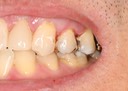

Ted Kanamori #30 pre-op

Ted Kanamori #31 caries removal

Ted Kanamori #31 prep

Ted Kanamori #31 finish

Ted Kanamori #31 finish buccal view